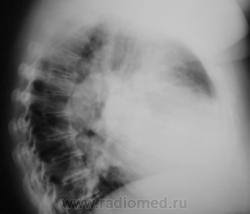

Это что? Левое предсердие?

На данной томограмме по правому контуру четко видна дуга увеличенного левого предсердия. Стрелки указывают на артериальные сосуды 3 сегмента. При лимфоаденопатии мы бы не увидели трахеобронхиальный угол и непарную вену справа. Стало быть: Cor mitrale с активной артериальной гипертензией МКК.

А что же тогда круглое, отмеченное стрелками в посте lupan?

Как это так это? Вторая дуга по правому контуру сердца возникает только от увеличенного левого предсердия. Пусть будет ДМПП, митральный порок, кардиомиопатия, кардиомидистрофия с расширением всех камер сердца. Давйте попросим контрастировать пищевод.

Конечно это дуга левого предсердия, но оценивать и ориентироваться  нужно на его толщину, а не поперечник. Конечно здесь все камеры увеличены, так как имеет место диффузное снижение тонуса миокарда, но относительно других камер увеличение небольшое, и имеет место дилятация, небольшая...

У меня получилось: увеличен левый желудочек (может и дилятирован) и левое предсердие (надуто, как мяч, скорее всего гипертрофировано, кривизна явно малого радиуса). Может не так померял?

Но мне задняя граница левого предсердия показалась ровно на половине проведенной вами линии. Согаситесь, что представить, себе в этом сдавшемся дилатированном сердце - ограниченный и настолько гипертрофированный участок - левое предсердие - все - таки трудно.